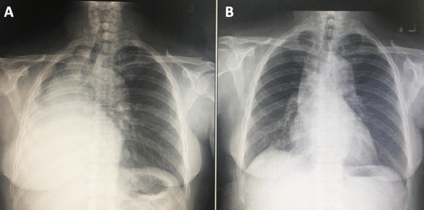

หญิงไทยคู่อายุ 48 ปี เป็นแม่บ้าน ภูมิลำเนาจังหวัดอุบลราชธานี มาโรงพยาบาลด้วยอาการหอบเหนื่อยขณะออกแรงมา 3 เดือน มีโรคประจำตัว ได้แก่ เบาหวานและความดันโลหิตสูงควบคุมได้ดี ไม่สูบบุหรี่ ปฏิเสธการเป็นวัณโรคหรือสัมผัสผู้ป่วยวัณโรคและไม่มีประวัติมะเร็งในครอบครัว 1 ปีก่อนมีไอแห้งเป็นๆ หาย ๆ ไม่มีไข้ ไม่เหนื่อย ไม่มีเจ็บหน้าอก 3 เดือนก่อน รู้สึกหายใจมีเสียงครืดคราด เหนื่อยเวลาออกแรง เดินได้ 200 เมตรต้องหยุดพัก ไม่มีไข้ ไม่มีไอเป็นเลือด ไม่มีน้ำหนักลด 1 เดือนก่อนไปพบแพทย์ที่โรงพยาบาลใกล้บ้าน ภาพถ่ายรังสีทรวงอกพบ right lung atelectasis (รูปที่ 1) และภาพถ่ายรังสีคอมพิวเตอร์ทรวงอก (computed tomography; CT) พบ endobronchial mass ที่ right main bronchus และ right lung atelectasis (รูปที่ 2) ได้รับการส่องกล้องหลอดลม (flexible bronchoscopy) พบ endobronchial mass at right main bronchus with total occlusion ผลการตรวจทางพยาธิวิทยาพบเป็น chronic inflammation จึงส่งมาตรวจเพิ่มเติมที่โรงพยาบาลศิริราช ตรวจร่างกายแรกรับ ไม่มีไข้, ความดันโลหิต 144/100 มม.ปรอท, ชีพจร 103 ครั้ง/นาที, อัตราการหายใจ 22 ครั้ง/นาที และ oxygen saturation 93% ไม่มีนิ้วปุ้ม ไม่บวม ตรวจระบบการหายใจพบ trachea shift to the right, decreased breath sound and vocal resonance on right lung with dullness on percussion ตรวจร่างกายระบบอื่นอยู่ในเกณฑ์ปกติ ตรวจ spriometry พบ severe restrictive ventilatory defect ผลการส่องกล้องหลอดลมพบรอยโรคดังรูปที่ 3

ภายหลังการทำหัตถการ อาการผู้ป่วยดีขึ้นทันที ภาพถ่ายรังสีทรวงอกดีขึ้นดังแสดงในรูปที่ 5 และได้ส่งปรึกษาแพทย์ศัลยกรรมทรวงอกเพื่อประเมินการรักษาโดยการผ่าตัด แต่พบว่ารอยโรคมีความเสี่ยงในการผ่าตัดสูง จึงพิจารณาติดตามอาการและให้การรักษาเฉพาะที่โดยการทำ rigid bronchoscopy ร่วมกับ tumor removal กรณีที่ก้อนมีขนาดใหญ่ขึ้น